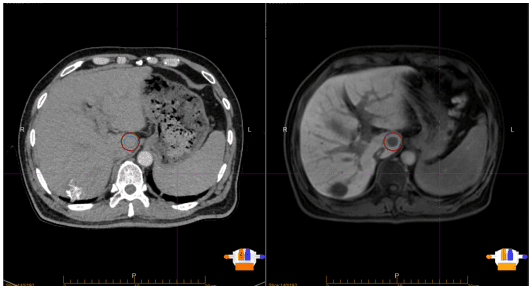

此次治疗针对的是一位肝脏转移瘤在常规CT定位图像上显影不清、边界模糊的患者,该难题曾使高精度放疗计划的制定面临巨大挑战。为解决这一难题,肿瘤中心团队创新性地启用了先进的磁共振模拟定位系统(MR-SIM)。磁共振成像(MRI)凭借其卓越的软组织分辨能力和多参数成像优势,清晰“勾勒”出CT难以显示的肝转移瘤的精确位置、大小和形态,为放疗团队提供了一份至关重要的“高清靶区地图”。基于这份精准的定位图像,团队为患者量身定制了立体定向体部放射治疗(SBRT)方案。

“当CT定位遇上肝转移瘤这类‘隐匿型’病灶时,磁共振定位技术展现出独特且不可替代的优势。”肿瘤中心成浩博士介绍,“它为我们‘照亮’了病灶,使得高精度、高剂量的SBRT治疗能够安全有效地实施,这是提升此类疑难患者疗效的关键一步。”